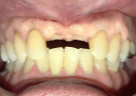

女性Tさん 60代(インプラント)

主訴

上の前歯の部分入れ歯が合わないので、インプラントにしたい。

治療内容

インプラントを4本埋入しました。

所感

骨の厚みが薄かったのですが、X-Guideを用い、正確に埋入することが来ました。

治療後「とてもきれいに出来てうれしかったです。話をしても、空気がもれず良くなりました。もう少し早く治すと良かったと思いました。」と、とても喜んでくださいました。

インプラント4本:¥363,000×4本=¥1,452,000(税込)

Before

インプラント埋入前

義歯を装着したところ

使用していた部分入れ歯

After

インプラント埋入後